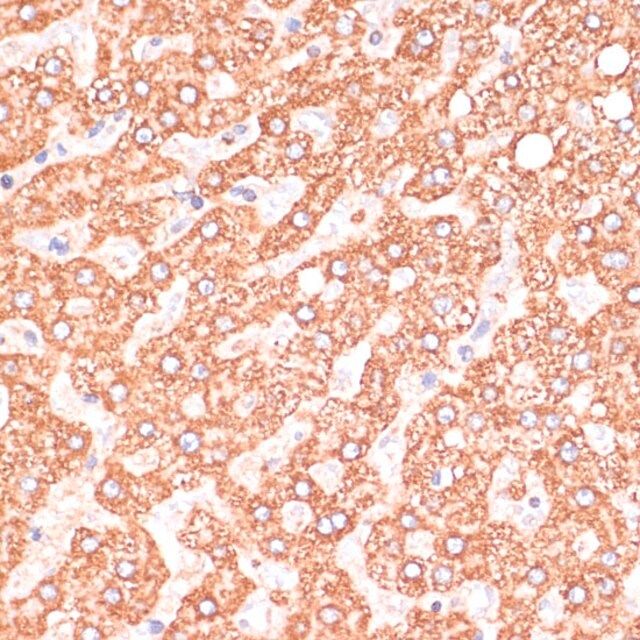

| technique(s) | immunofluorescence: 1:50-1:200 immunohistochemistry: 1:50-1:200 western blot: 1:500-1:2000 |